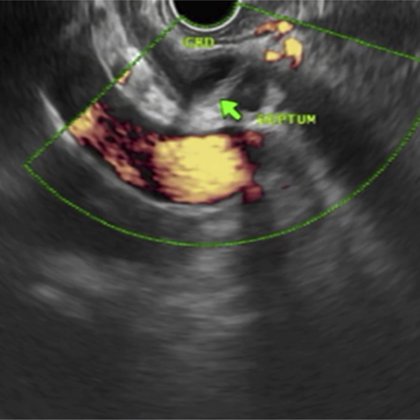

Quite a sticky situation! Impacted basket in pancreatic duct @SIAGPK @Muhammad_Asim_s